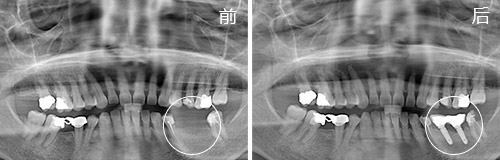

种植情况:全口种植,即拔即种,植骨